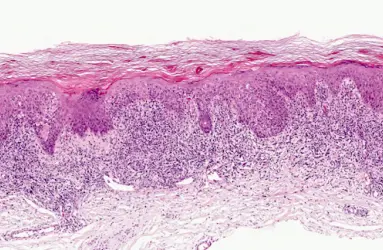

- Sedef (Psoriasis) Hastalığı

- Liken Planus

- Seboreik Dermatit

- Atopik Dermatit

- Kontakt Dermatit